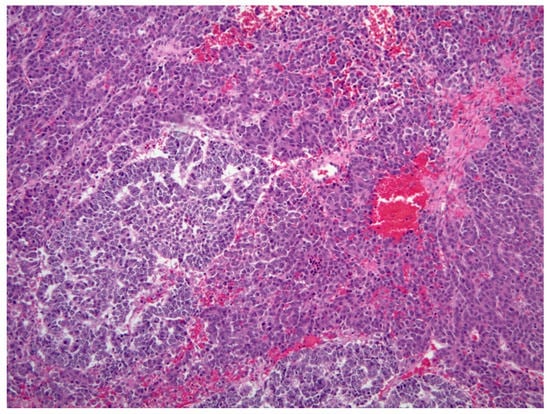

5.2.5. Histopathology and Immunohistochemistry